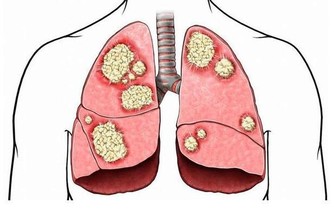

這一種人,千萬別側睡!!!你會後悔終生的…看了就明白了!!

頸椎病患者更適合仰臥,這樣可以順應頸椎的生理彎曲,為達到枕頭支撐頸部的目的,患者最好將蕎麥皮枕頭的形狀稍加整理,使其形成一個中間凹、兩邊凸的形狀,高起的部分相當於自己的拳頭。睡眠時儘量枕著中間凹的部位,開始時不太習慣,經過長期適應,可以最大程度減少睡眠過程中的翻身動作。 蕎麥皮枕頭的適應性強,填充枕頭時,不要填得太滿,否則影響其塑形,填充約70%即可。(蘇玉梅)